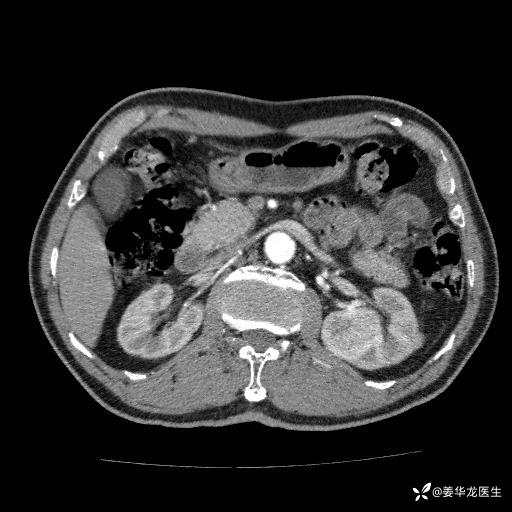

左肾中心型肾门部肿瘤39mm×34mm×36mm,右肾GFR25ml/min,部分切还是全切?

患者75岁老年男性,体重50kg,无高血压、肾病、糖尿病等基础病,检查发现左肾中心型肾门部肿瘤,右肾GFR只有25ml,无肉眼血尿,无镜下血尿。入院验血常规检查均正常,包括肾功能,肌酐102.7umol/L.

二、左肾肿瘤与左肾集合系、左肾动静脉关系密切,左肾部分切除术可行吗?成功率有多大?成功部分切后,肾功能还有多少?